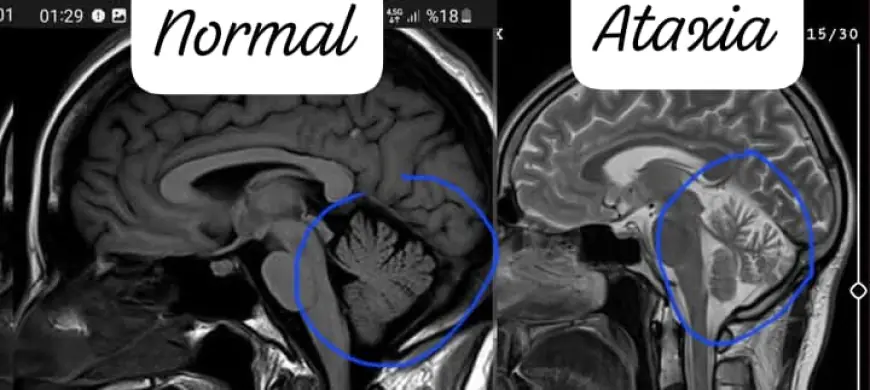

Cekilen MR(manyetik rezonans) sonucunda beyinciğimin aşırı küçük olduğu ve konuşma bozukluğumun daha da artacağı söylendi.

Oğlum 18 yaşında spino serebellar ataksi tip 2 hastası.15 yaşında covid sonrası ellerinde titreme, bardak tutamama, ayağa kalktığında yürümeye başladığında sağa sola savrularak yürüme şeklinde başladı.Nöroloji bölümüne gittik manyetik rezonans çektirdik, mr.inda da serebellar atrofi(beyincik küçülmesi) denildi.